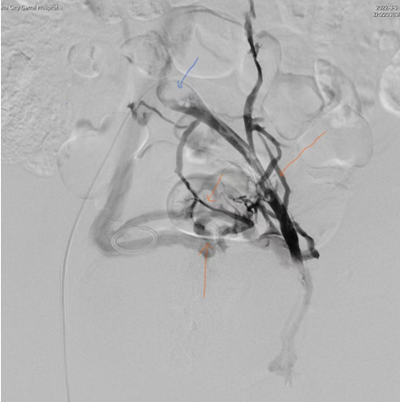

治疗前造影图。图像所示为导管插入到左髂外静脉造影,多支侧支血管开放(橙色箭头所示),左髂总静脉近心端充盈缺损(蓝色箭头处)。